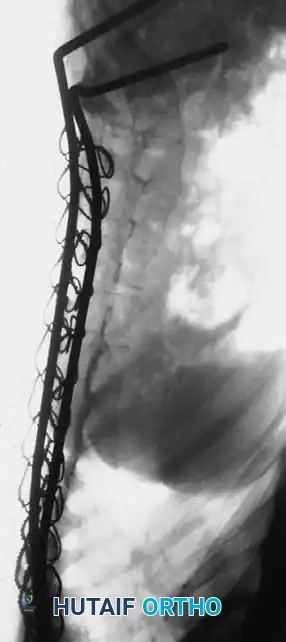

Associated Surgical & Radiographic Imaging

Hutaifortho's Orthopaedic Diagram